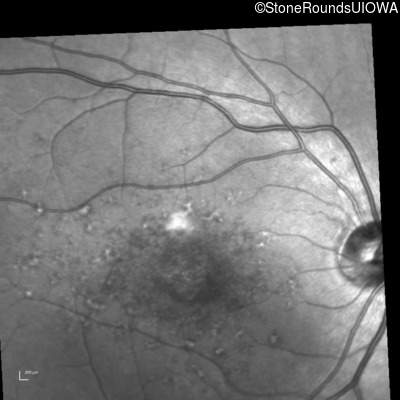

Infrared Fundus Photograph - Right - 20/80 -1

Exemplar